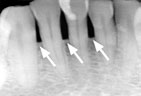

Periodontitis Periodontitis

Advanced Periodontitis Advanced Periodontitis